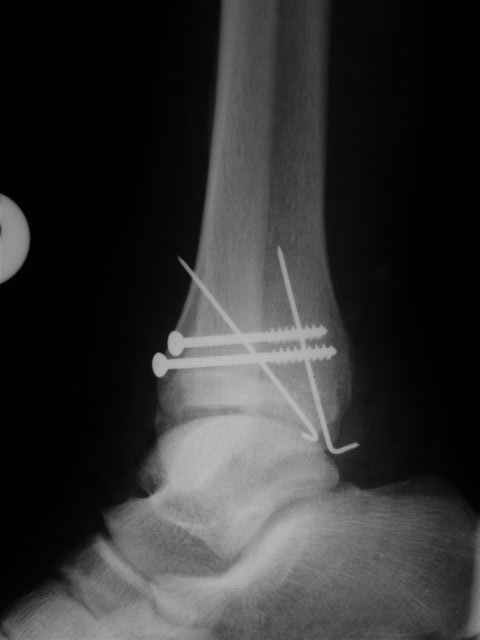

> интересуюсь тактикой лечения повреждений голеностопного сустава.

Ничего сверхъестественного, но если есть интерес, то в понедельник пересниму Рг-граммы и отправлю.

Я предупреждал, что ничего сверхъестественного. Каюсь, что одна из спиц прошла несколько дальше, чем нужно было, но главное - перелом стабилизирован и больной работает суставом в полном объёме, несмотря на представленную раннее травму коленного сустава.